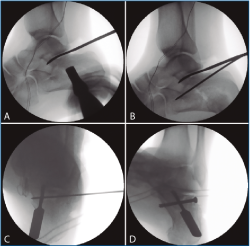

En los 4 casos con osteosíntesis percutánea, una vez levantado el fragmento, se realiza una fijación provisional con agujas de 1,8 mm (Figuras 4B y 4C), que podemos emplear, además, para manipular el fragmento y mejorar la corrección. A continuación, se procede a la inserción de los tornillos canulados de 3,5 mm de lateral a medial, solidarizando el fragmento lateral con el anteromedial (Figura 4D). Se debe combinar la visión artroscópica con una visión radiológica que nos confirme la posición y longitud adecuada de los tornillos.

Figura 4. A: control de escopia intraoperatoria (perfil) de la lesión reducida con ayuda de periostotomos; B: control de escopia intraoperatoria (perfil) tras insertar la primera aguja mientras se mantiene la reducción con un periostotomo; C: control de escopia intraoperatoria (axial de calcáneo) tras insertar la primera aguja mientras se mantiene la reducción con un periostotomo; D: control de escopia intraoperatoria (axial de calcáneo) tras colocación del primer tornillo de osteosíntesis.

En los 2 casos restantes, tras la reducción controlada tanto con escopia como con artroscopia (Figuras 5A y 5B), se procedió a la inyección de hidroxiapatita, como describe la técnica de la calcaneoplastia.

Figura 5. A: control de escopia intraoperatoria (perfil) de la localización óptima para insuflar el balón de calcaneoplastia; B: control de escopia intraoperatoria (perfil) tras la insuflación del balón de calcaneoplastia.